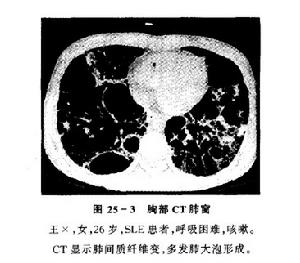

非特異性間質性肺炎影像學特點:高分辨CT顯示雙肺對稱性毛玻璃影或雙肺肺泡腔的實變影。

電子顯微鏡鏡下肺炎支原體三、咳嗽以夜間為重,偶爾有少量黃粘痰,入院前1個月出現活動後氣短,漸加重至上一層樓梯亦有症狀,同時伴胸背持續鈍痛。病程中有間斷髮熱,無關節肌肉痛史。體格檢查:輕度紫紺,無杵狀指,雙肺可聞爆裂音。血ANA、抗ds-DNA、RF及抗ENA均陰性。胸片示雙中下肺間質紋理厚,呈磨玻璃樣改變伴小斑片結節狀影。HRCT(圖4)見右肺中葉、左肺舌葉及雙肺下葉密度增高呈磨玻璃樣改變,雙肺支氣管血管紋理增厚,右肺中葉內側段支氣管擴張,雙側胸膜不規則增厚,縱隔內及雙肺門淋巴結多發鈣化。血氣分析PaO261.4mmHg。BALF細胞總數1.27×109/L,淋巴細胞占32%,中性細胞占47%,巨噬細胞占21%;T淋巴細胞亞群分析:CD417.6%,CD877.7%,CD4∶CD8=0.227。經支氣管肺活檢(TBLB)病理所見為少許血管及破碎的支氣管黏膜上皮呈急性及慢性炎。經電視引導下胸腔鏡肺活檢確診為非特異性間質性肺炎。

2.HRCT的主要特徵是:雙側、對稱、主要在下肺的網狀陰影,伴牽拉性支氣管擴張和下葉體積減少,通常為瀰漫性或胸膜下分布,但有時病變並不累及胸膜下肺組織。